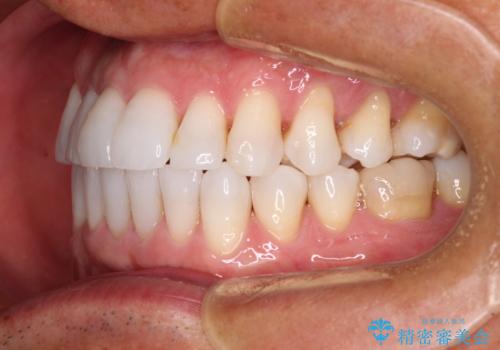

- 治療途中の前歯と上下前歯のデコボコ気にして来院された患者様です。

前歯のデコボコはインビザラインにより歯列を整え、その後に、前歯などをオーダーメイドタイプのオールセラミッククラウンにて補綴治療することとしました。

長時間のマウスピース装着に協力いただき、短期間で歯列をしっかりと改善することができました。

ホームホワイトニングを併用していただいたので、とても明るい口元に仕上がり、患者様には大変満足していただきました。